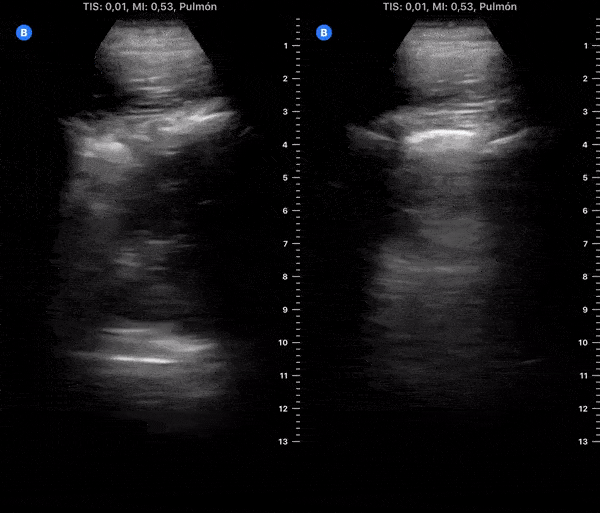

COVID 19 Lung US Disease Progression - Day 13

Day 13 after #COVID diagnosis. Lesser cough, weakness, nausea & diarrhea. No dyspnea or red flag symptoms. No fever. SpO2 97%. #POCUS update: 2 subpleural consolidations (resolving), thick pleura & bilateral scattered B-lines. @yaletung